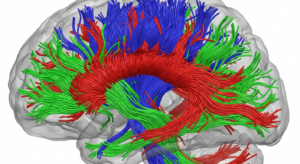

📊 Visualización Gráfica 1: Conectividad Estructural Humana (Tractografía)

Enseguida, se exhibe una visualización creada por técnicas avanzadas de DTI, ilustrando la compleja arquitectura de la materia blanca cerebral humana.

¡Observa! Es una imagen en alta fidelidad, mostrando la tractografía, detallando las vías de comunicación más importantes entre y dentro de los hemisferios cerebrales.

Mapa del Cerebro Humano, en tractografía. Esta imagen, creada con Tensor de Difusión (DTI), ilustra la compleja conexión estructural (la materia blanca, ¿sabes?). Los colores revelan la dirección de los tractos axonales: rojo, para la comunicación izquierda-derecha (como el cuerpo calloso), verde para adelante-atrás y azul para arriba-abajo. Este «cableado» es la base física donde actúan las redes funcionales.